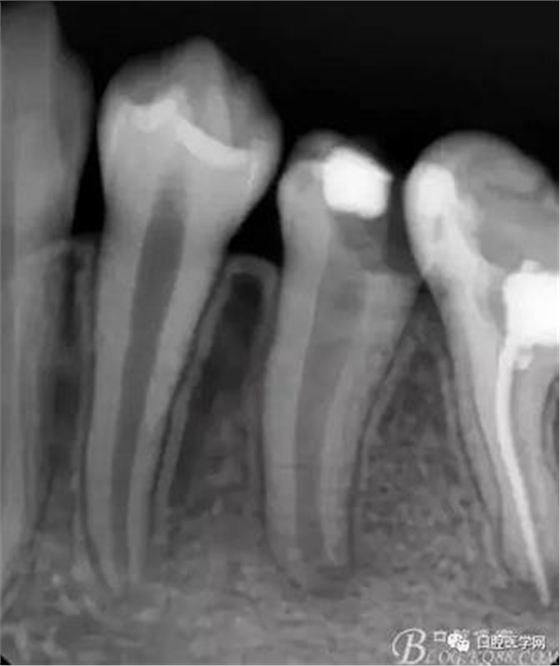

X檢查:

36根管治療遺漏根管,欠填以及超填,根尖有陰影 ,有繼發(fā)齲;35根尖部有陰影,未行根管治療,有繼發(fā)齲已穿髓

診斷:35,36為慢性根尖炎